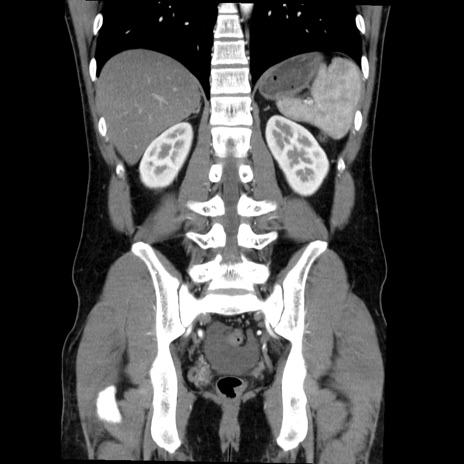

症例36(冠状断像)

【症例】20歳代 男性

【主訴】心窩部痛

【現病歴】今朝より上腹部痛あり。一旦軽快していたが再度出現したため救急要請。昨日夕に白身の魚を含む刺身を食べた。

【身体所見】BP 136/89mmHg、HR 74/min、BT 37.0℃、腹部:膨満、軟、心窩部に圧痛あり。反跳痛なし、筋性防御なし、腸雑音やや亢進あり。

【データ】WBC 17700、CRP 0.48